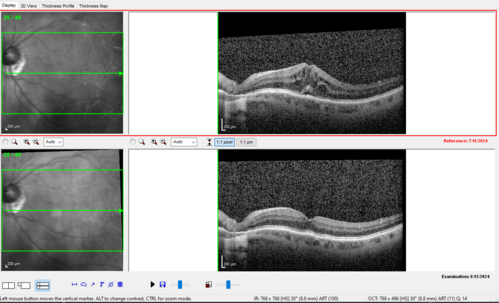

Latanoprost induced CME

89 year old man with CME from latanoprost that cleared within one month of stopping the medication